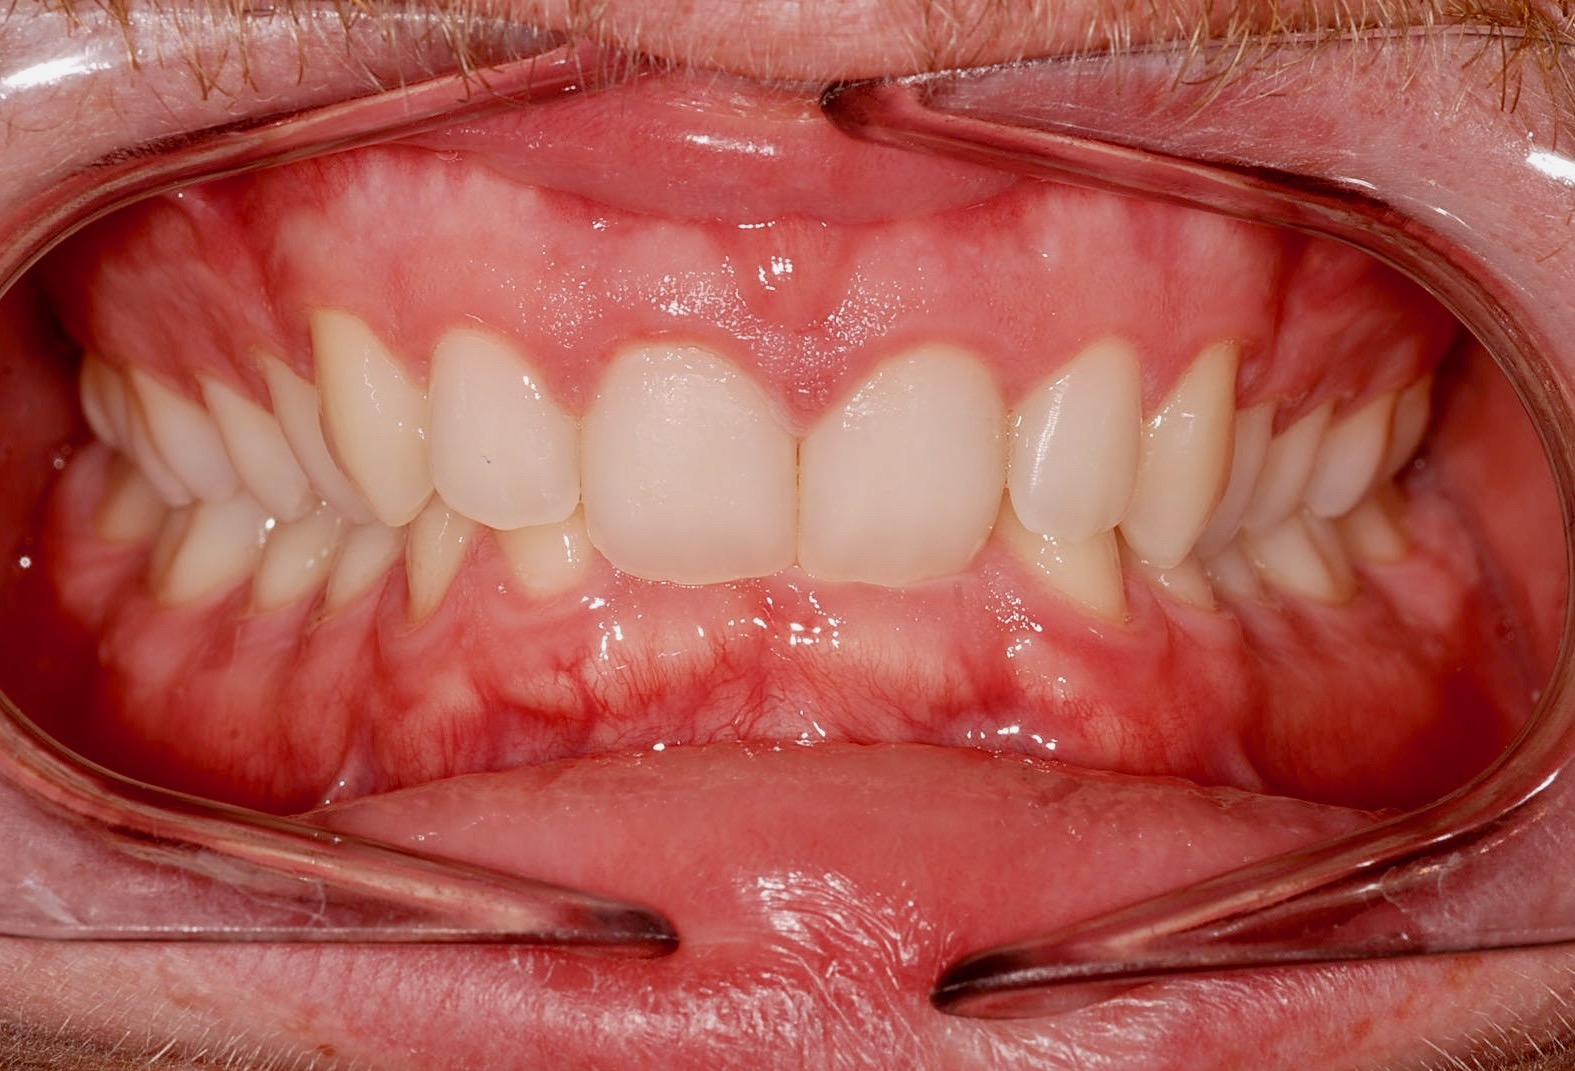

Class II subdivision malocclusions can be difficult to treat because of their asymmetric occlusal relationships. An accurate diagnosis, etiologically based when possible, is essential to perform a correct and efficient orthodontic treatment.

The aim of this article is to illustrate a case report treated with customized lingual brackets in association with a simple vestibular device.